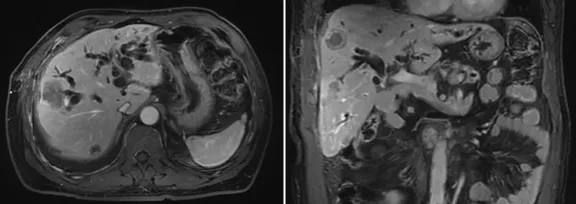

增強(qiáng)CT結(jié)果

壺腹部腺癌術(shù)后改變,左右肝管匯合部異常信號,不除外復(fù)發(fā)可能;考慮肝內(nèi)多發(fā)轉(zhuǎn)移瘤形成

所見右側(cè)胸腔積液,右下肺片狀異常信號,建議進(jìn)一步胸部檢查